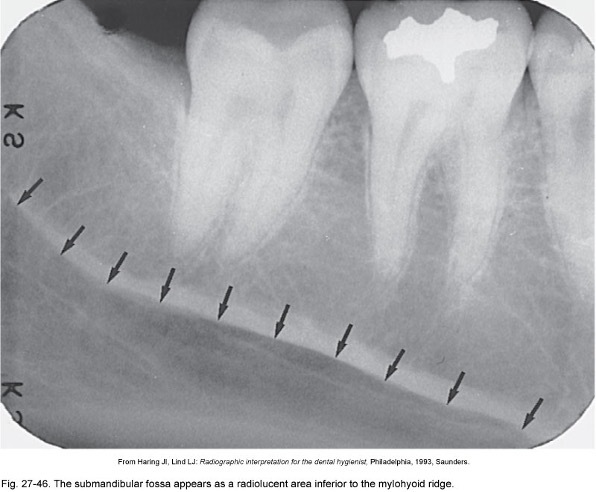

24

Q

What is this a picture of and what is it? What is an example?

A

Fossa- broad, shallow, depression of bone

ex. submandibular fossa

How well did you know this?

What is this a picture of?

Submandibular Fossa